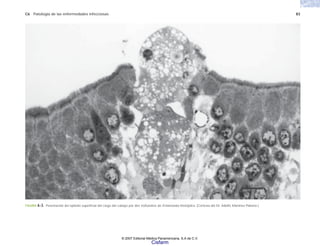

C6 Patología de las enfermedades infecciosas 83

FIGURA 6-3. Penetración del epitelio superficial del ciego del cobayo por dos trofozoítos de Entamoeba histolytica. (Cortesía del Dr. Adolfo Martínez Palomo.)